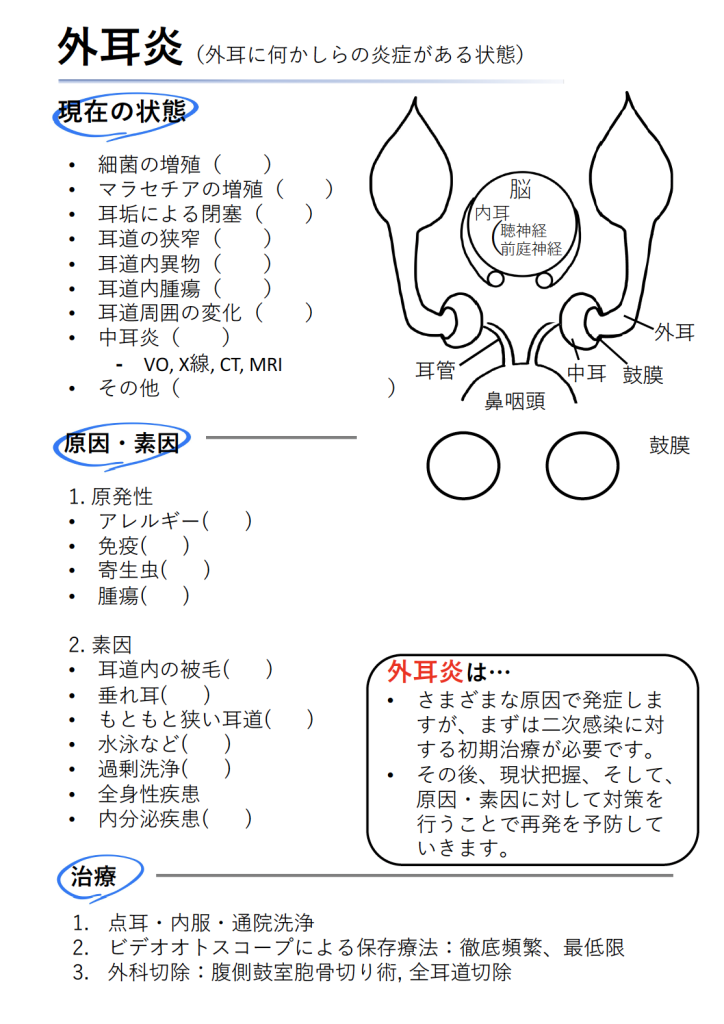

まず簡単に解剖学的な図をイメージしてもらうと分かりやすいです。

下図の通り、いつも見ている耳(耳介)の奥には耳道という長いトンネルが続いており、途中でL字に曲がって、突き当たりに鼓膜があります。

鼓膜の奥には骨で囲まれた空間があり、鼓膜より外を外耳、鼓膜より中を中耳とイメージするとよいでしょう。

中耳は耳管という細い管で鼻の奥(鼻咽頭)につながっており、鼻と同じ粘膜が内張しています。

さらにこれら内側には脳があり、脳と中耳の間の頭蓋骨の中に内耳があります。

内耳には、聴神経や平衡感覚を司る前庭神経が存在します。

基本的にこの外耳に何かしらの炎症がある場合を外耳炎と呼びます。

外耳炎はさまざまな原因で発症しますが、その要因は素因性、原発性、二時性、永続性などに分類されます。

これらは初診日の1日だけでは分からないため、まずはできるだけ現在の状態を確認し、二次的な変化から制御することが重要です(二次感染や炎症の制御)。

二次的な変化が制御できた後に、原発性や素因性、永続性の要因を確認・対処することで、再発を予防することにつながります。

基本的に外耳炎の治療を大きく分けると、以下の3つがあります。

- 点耳・内服・通院での耳洗浄

- ビデオオトスコープによる保存療法

- 外科切除